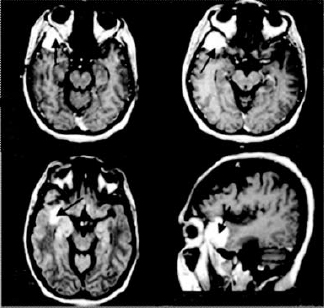

Se realizó estudio de resonancia magnética cerebral (figura 1) en el cual se evidenció una imagen hiperintensa en T1 en la región temporal derecha, con importante edema perilesional, efecto de masa local, sin desviación de línea media. Se realizó un diagnostico inicial de meningioma de ala del esfenoides derecho. Se decidió hospitalizar, se inician medidas antiedema cerebral y monitoría neurológica.

Figura 1. Imagen hipertensa con edema perilesional temporal derecho.